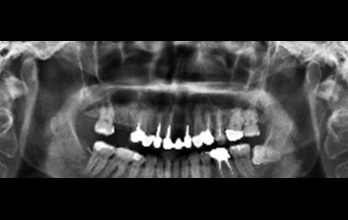

治療前,全口X光片。